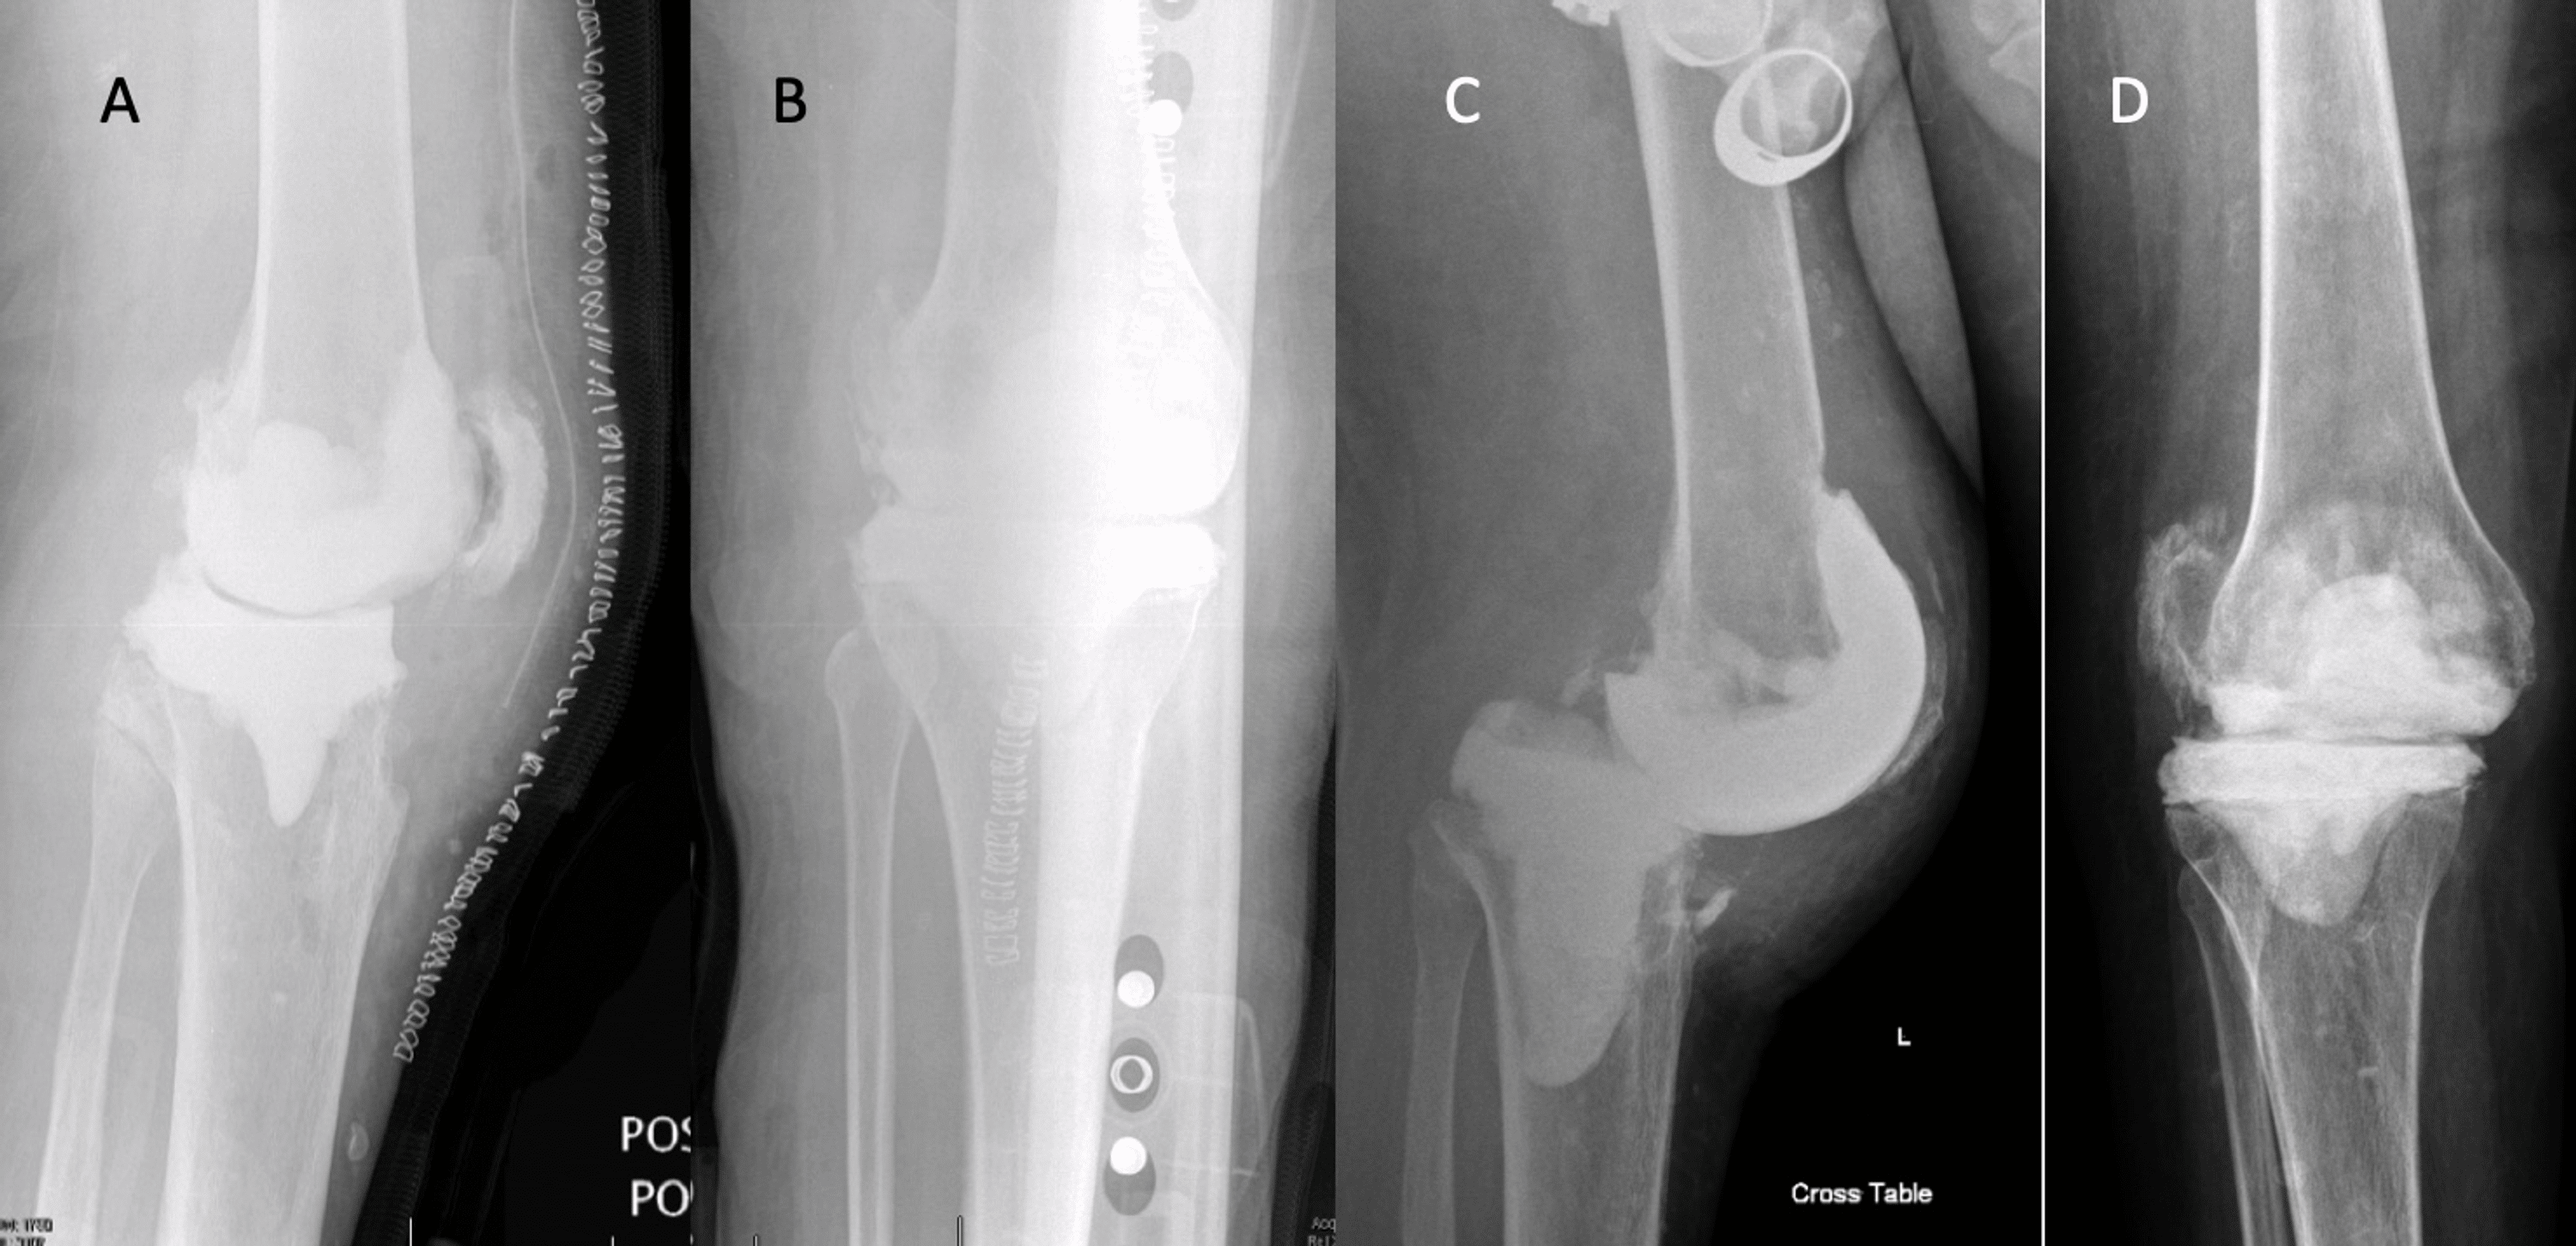

Retained Antibiotic Spacers After Total Hip and Knee Arthroplasty Hip Spacer Complications The rehabilitation program following hip spacer implantation emphasizes early, controlled functional range of motion to prevent hip. The aim of this retrospective study was to identify and evaluate complications after hip spacer implantation other than reinfection. We aimed to evaluate the clinical outcomes of different spacer. Temporary spacers used in the staged revision of a hip prosthetic joint infection (pji). Hip Spacer Complications.

Retained Antibiotic Spacers After Total Hip and Knee Arthroplasty Hip Spacer Complications The aim of this retrospective study was to identify and evaluate complications after hip spacer implantation other than reinfection. We aimed to evaluate the clinical outcomes of different spacer. Temporary spacers used in the staged revision of a hip prosthetic joint infection (pji) have been associated with several mechanical. The use of “functional” spacers may allow patients to return to. Hip Spacer Complications.

Retained Antibiotic Spacers After Total Hip and Knee Arthroplasty Hip Spacer Complications The rehabilitation program following hip spacer implantation emphasizes early, controlled functional range of motion to prevent hip. We aimed to evaluate the clinical outcomes of different spacer. Temporary spacers used in the staged revision of a hip prosthetic joint infection (pji) have been associated with several mechanical. The use of “functional” spacers may allow patients to return to daily living. Hip Spacer Complications.

Retained Antibiotic Spacers After Total Hip and Knee Arthroplasty Hip Spacer Complications The aim of this retrospective study was to identify and evaluate complications after hip spacer implantation other than reinfection. The use of “functional” spacers may allow patients to return to daily living while optimizing their health for revision surgery. The rehabilitation program following hip spacer implantation emphasizes early, controlled functional range of motion to prevent hip. We aimed to evaluate. Hip Spacer Complications.